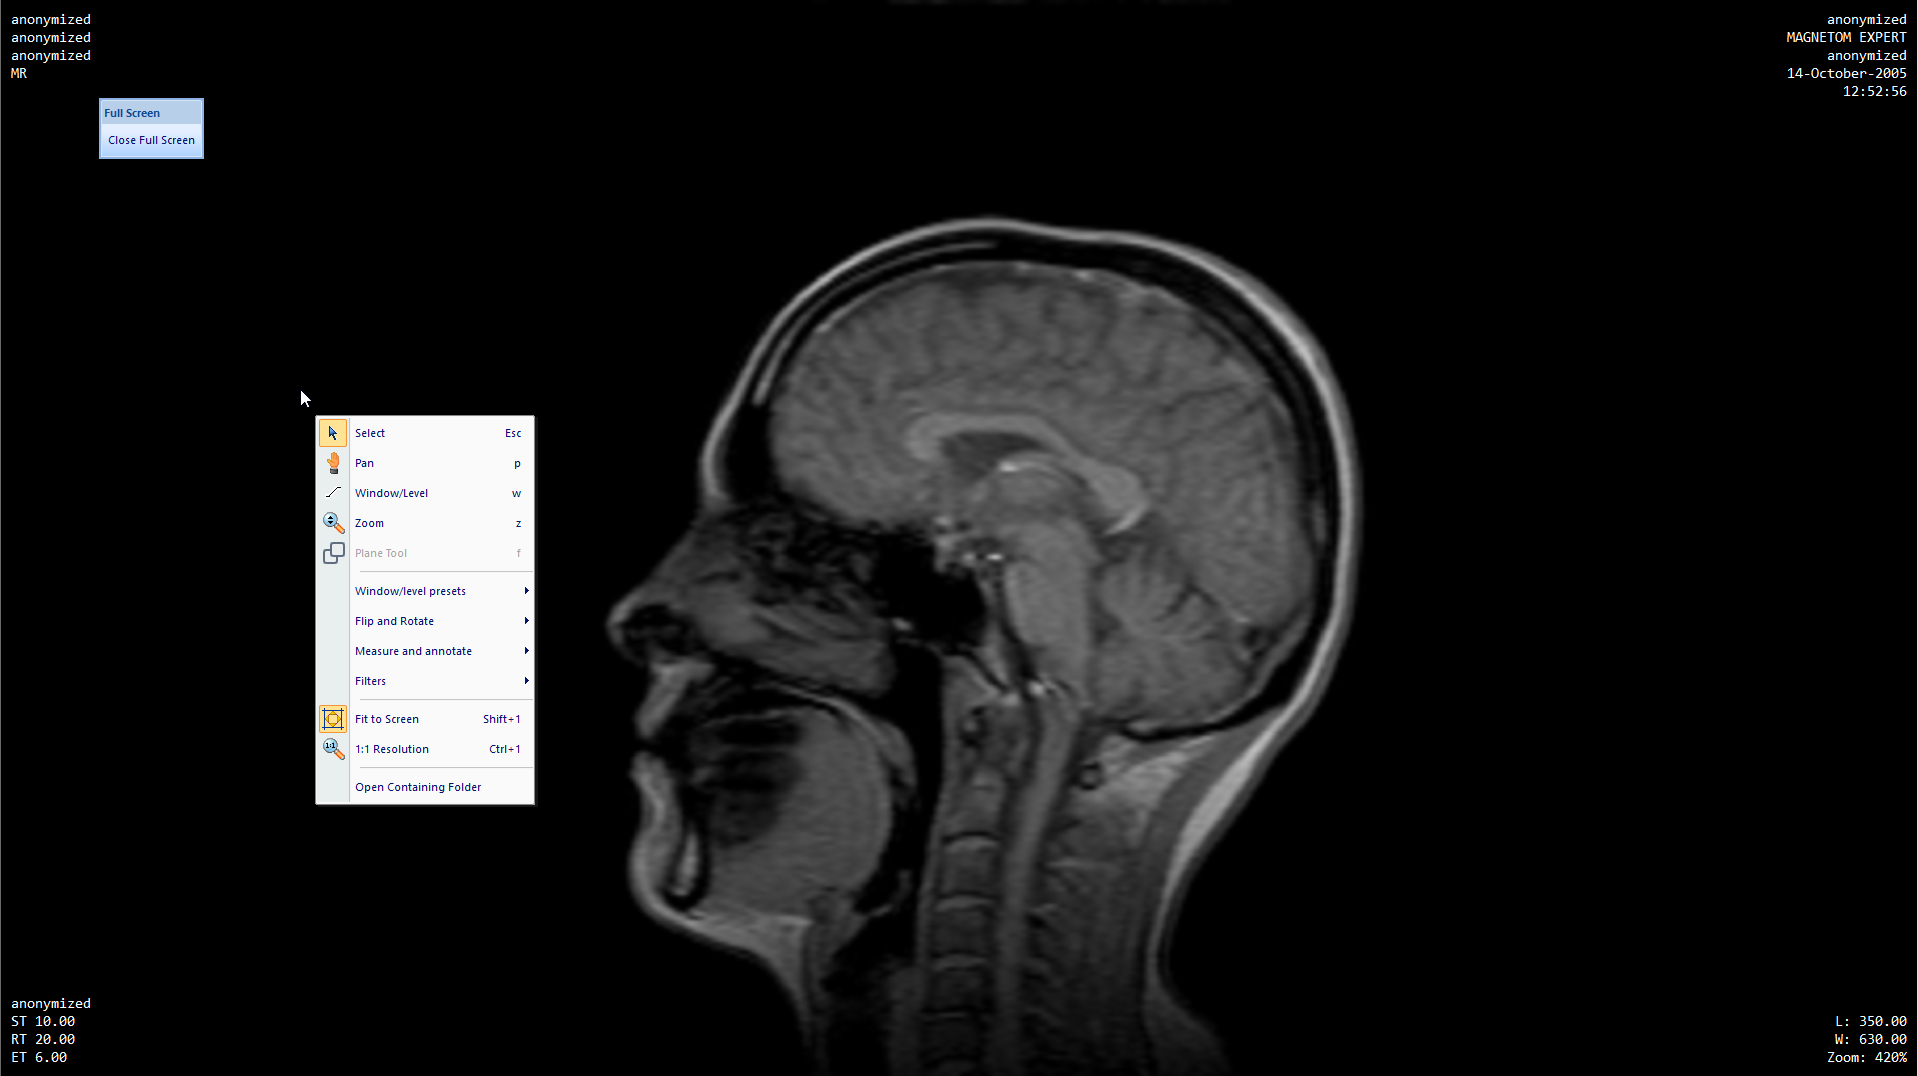

17/06/2019 · more than a dicom viewer, athena dicom essential marks a new generation of software to view and manipulate medical images. Export dicom to jpeg, bmp, png, gif, … Ginkgo cadx is a free open source dicom viewer software for windows, linux, and macos. 07/06/2020 · export dicom files to images, movies, clipboard and text. Microdicom is a free dicom viewer software which lets you view single and multiple dicom files. No downloads or installation required. In this software, you can view medical scan data (mri, ultrasound, etc.) present in a dicom (.dcm) file. Dicom is an acronym for digital imaging and communication in medicine, and it’s a powerful free medical software that media freeware developed for windows devices. Radiant dicom viewer is another good dicom viewer with a handful of necessary features to view. Images can be send to the windows clipboard and after that paste in other applications. It is extremely fast, runs from cd/dvd media without installation on windows 7, windows 8, windows 8.1, windows 10 and windows 11 systems and does not have any additional software or programming requirements (e.g. Our software can be used to convert jpeg, bmp images to dicom images. Xmedcon is a dicom viewer that provides dicom images conversion functionality, it was written with c language and works flawlessly, it gives the user the option as well to export to jpg still image or gif animated image.

Radiant dicom viewer is another good dicom viewer with a handful of necessary features to view. Additionally, the app is suitable for anyone working in the health sector, and it can be helpful to them in several ways with medical image viewing, data … It is extremely fast, runs from cd/dvd media without installation on windows 7, windows 8, windows 8.1, windows 10 and windows 11 systems and does not have any additional software or programming requirements (e.g. Everything works locally, nothing is uploaded to any server. 17/06/2019 · more than a dicom viewer, athena dicom essential marks a new generation of software to view and manipulate medical images. Simply select any file or folder with dicom images. A free dicom viewer, for viewing images on windows, mac or linux, without any downloads or program installs. Xmedcon library has been used in several projects and proven to be a … Microdicom is a free dicom viewer software which lets you view single and multiple dicom files. No downloads or installation required. Xmedcon is a dicom viewer that provides dicom images conversion functionality, it was written with c language and works flawlessly, it gives the user the option as well to export to jpg still image or gif animated image. Dicom is an acronym for digital imaging and communication in medicine, and it’s a powerful free medical software that media freeware developed for windows devices. Export dicom to jpeg, bmp, png, gif, …

In this software, you can view medical scan data (mri, ultrasound, etc.) present in a dicom (.dcm) file.

Microdicom dicom viewer can export dicom images to common graphics formats and videos. Xmedcon is a dicom viewer that provides dicom images conversion functionality, it was written with c language and works flawlessly, it gives the user the option as well to export to jpg still image or gif animated image. It’s a program that let users conveniently access medical data. A free, browser based dicom viewer. Dicom is an acronym for digital imaging and communication in medicine, and it’s a powerful free medical software that media freeware developed for windows devices. Ginkgo cadx is a free open source dicom viewer software for windows, linux, and macos. Everything works locally, nothing is uploaded to any server. In this software, you can view medical scan data (mri, ultrasound, etc.) present in a dicom (.dcm) file. No downloads or installation required. It is extremely fast, runs from cd/dvd media without installation on windows 7, windows 8, windows 8.1, windows 10 and windows 11 systems and does not have any additional software or programming requirements (e.g. 17/06/2019 · more than a dicom viewer, athena dicom essential marks a new generation of software to view and manipulate medical images. 07/06/2020 · export dicom files to images, movies, clipboard and text. Export dicom to jpeg, bmp, png, gif, …